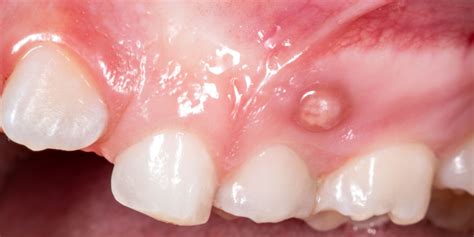

Una fístula dental es un pequeño canal que se forma desde la zona infectada del diente, que suele coincidir con el ápice de la raíz, hasta la superficie exterior de la encía. La fístula dental tiene el aspecto de una ampolla llena de pus en la boca, similar a un grano de pus. El pasaje actúa como depósito de pus y a medida que se llena, se forma una pequeña protuberancia en forma de grano cerca de las encías.

Una fístula dental es una pequeña abertura o canal anormal que se forma en la encía o en la región cercana a la raíz de un diente infectado. Esto es una fístula dental, o absceso periapical, es una acumulación de pus en un tejido periodontal, que puede abrirse y generar una vía de salida del pus, lo que provoca dolor. Una fístula dental es una afección oral que implica la formación de un conducto anormal entre el diente y el exterior de la boca.

Al principio, las encías se inflaman ligeramente y enrojecen. Al principio, la zona afectada se hincha. Las encías se enrojecen y hay una sensación de tensión en el diente. A continuación, se forma una ampolla en la encía, encima o debajo del diente afectado, que se llena de pus a medida que avanza. La fístula al aparecer se presenta normalmente en la encía, en la cima superior del diente. Se trata, como bien indicábamos, de un bulto con pus producido por diferentes razones.

Si se aplica mucha presión, el pus drena hacia la cavidad oral. Cuando se produce una infección dental, generalmente aparece asociada una hinchazón dentro y alrededor del sitio infectado. Un absceso dental es una acumulación de pus causada por una infección bacteriana en el tejido dental. En el caso de una fístula dental, el absceso puede manifestarse como una protuberancia roja y dolorosa en las encías cerca del diente afectado. Esta protuberancia puede estar acompañada de sensibilidad al tacto y al calor, así como de hinchazón en el área circundante.